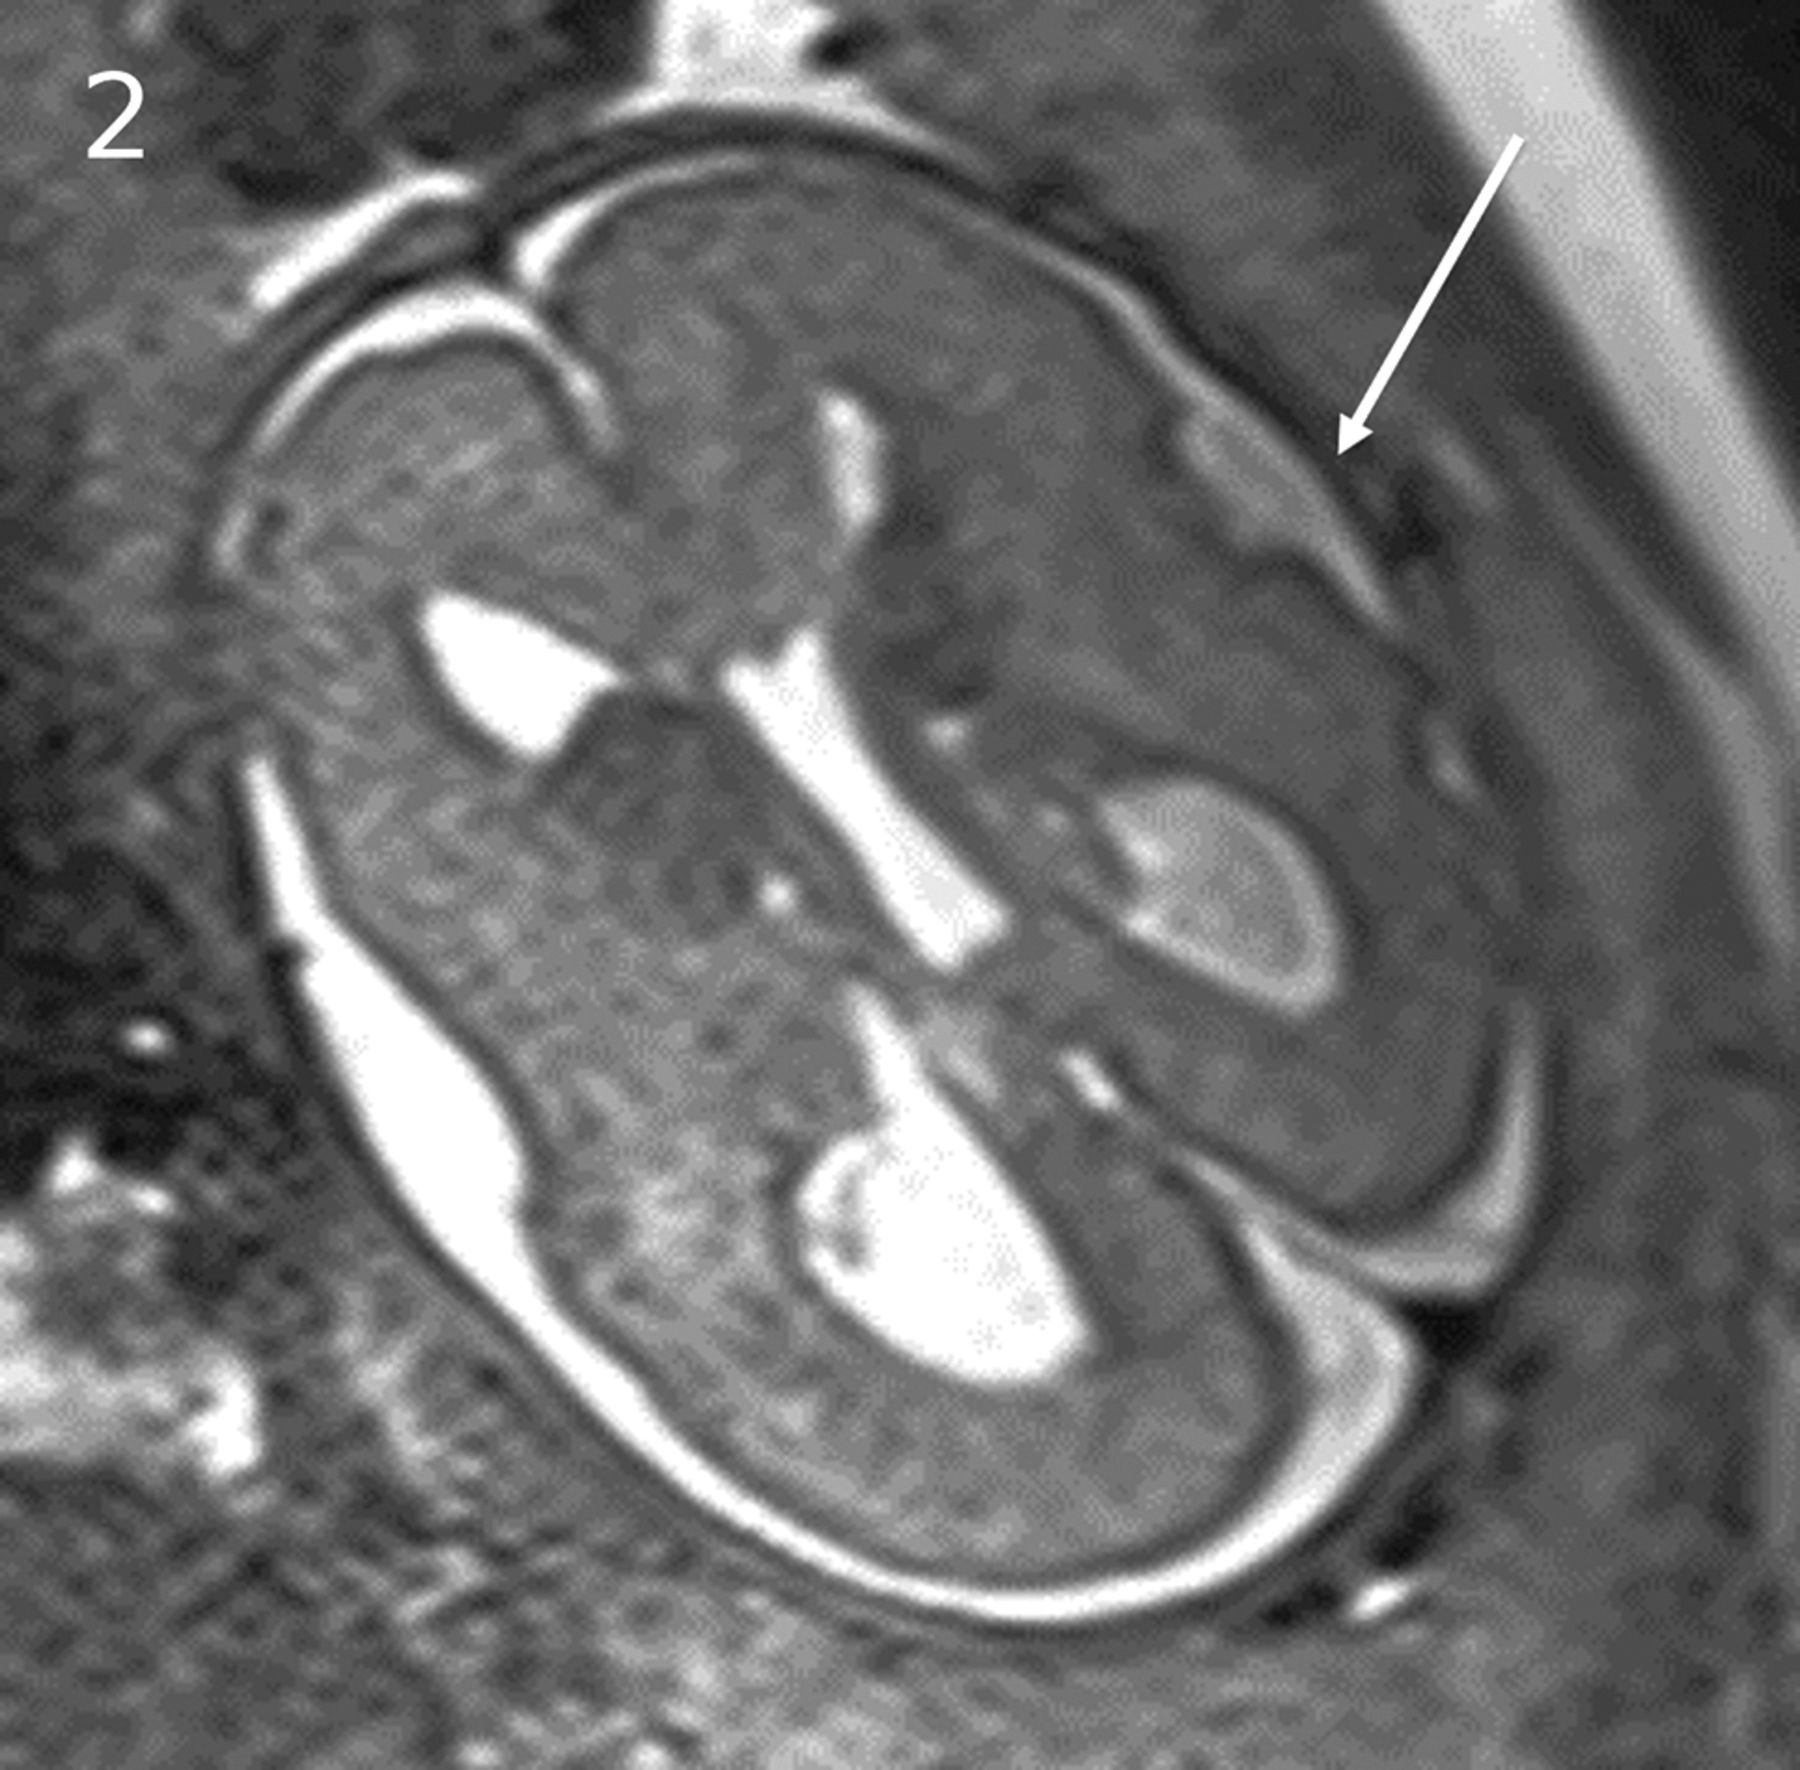

Subjects 1–8 had fronto-occipital head dimension measurements of ≥2 SDs greater than the mean. Of 5 cases with genetic testing, an MTOR or PI3KCA mutation was identified in 3, with megalencephaly, polymicrogyria, polydactyly, and hydrocephalus syndrome diagnosed prenatally in case 2 because of sonographically demonstrated postaxial polydactyly (Figs 1 and 2). Tuberous sclerosis was confirmed on genetic testing in 2 cases with cardiac rhabdomyoma, and a putative diagnosis was made in a third case with fetal hemimegalencephaly, a markedly enlarged ipsilateral GE, and a cardiac rhabdomyoma (Fig 3). In 2 subjects with large head sizes and no genetic testing, megalencephaly and hemimegalencephaly were present on postnatal imaging.

PIK3CA pathogenic variant. Case 2 at 31 weeks 3 days' gestation. Megalencephaly, polymicrogyria, polydactyly hydrocephalus syndrome due to a PIK3CA heterozygous pathogenic variant. The fronto-occipital diameter is >6 SDs above the mean for gestation. Enlarged bilateral ganglionic eminences (arrows, A) are seen on T2-weighted single-shot FSE and DWI (A and B). Diffusion-weighted b = 0 image (C) and T2*-weighted EPI (D) confirm the absence of hemorrhage as the cause for ganglionic eminence enlargement. Abnormal opercularization is present with Sylvian fissures lined by peri-Sylvian polymicrogyria (E). Postaxial polydactyly is seen on sonography with arrow indicating a rudimentary sixth digit medial to the fifth digit of the hand (F).

MTOR/PROS pathway mutations. Smith-Kingsmore syndrome (case 5) at 25 weeks' gestation demonstrates enlarged GEs on DWI and T2-weighted single-shot FSE. There is bilateral underopercularization and left peri-Sylvian polymicrogyria (arrow). The right hemisphere is mildly overgrown.